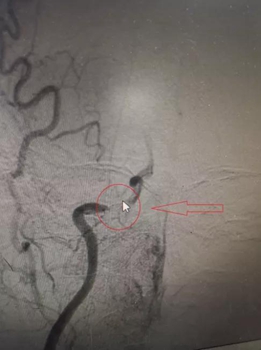

术前影像                影像

与家属详细解释沟通并取得支持后,由我院神经外科主任、神经介入中心主任廖驭国带领神经内科一区副主任刘国超以娴熟的技术为患者施行急诊机械取栓术+右侧颈内动脉支架植入术,在短短2个小时的高效配合下实现闭塞血管再通,术后患者言语、左侧肢体无力明显好转。